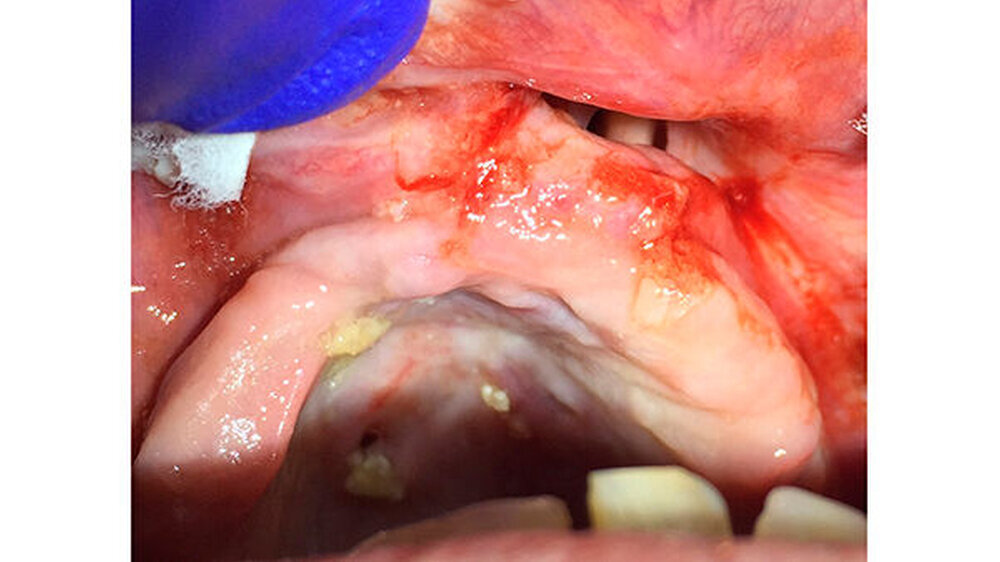

Die Patientin wurde dann über acht Wochen mit Clindamycin behandelt. Eine in der Zahnarztpraxis erfolgte plastische Deckung der MAV platzte nach zwei Tagen post operationem wieder auf. Ihr Allgemeinzustand verbesserte sich trotzdem erheblich. Im Unterschied zu vorher konnte sie den Weg vom Wartezimmer in den Behandlungsstuhl selbstständig gehen.

Dieser Fall zeigt deutlich, wie wichtig es ist, dass das Klinik- und Pflegepersonal umfassend geschult ist, wie eine Prothese richtig und vor allem regelmäßig zu reinigen und zu kontrollieren ist. Hier hatte der nicht mehr passende Zahnersatz zu massiven Druckstellen geführt, was sich schließlich in einer deutlichen Gewebedestruktion zeigte.